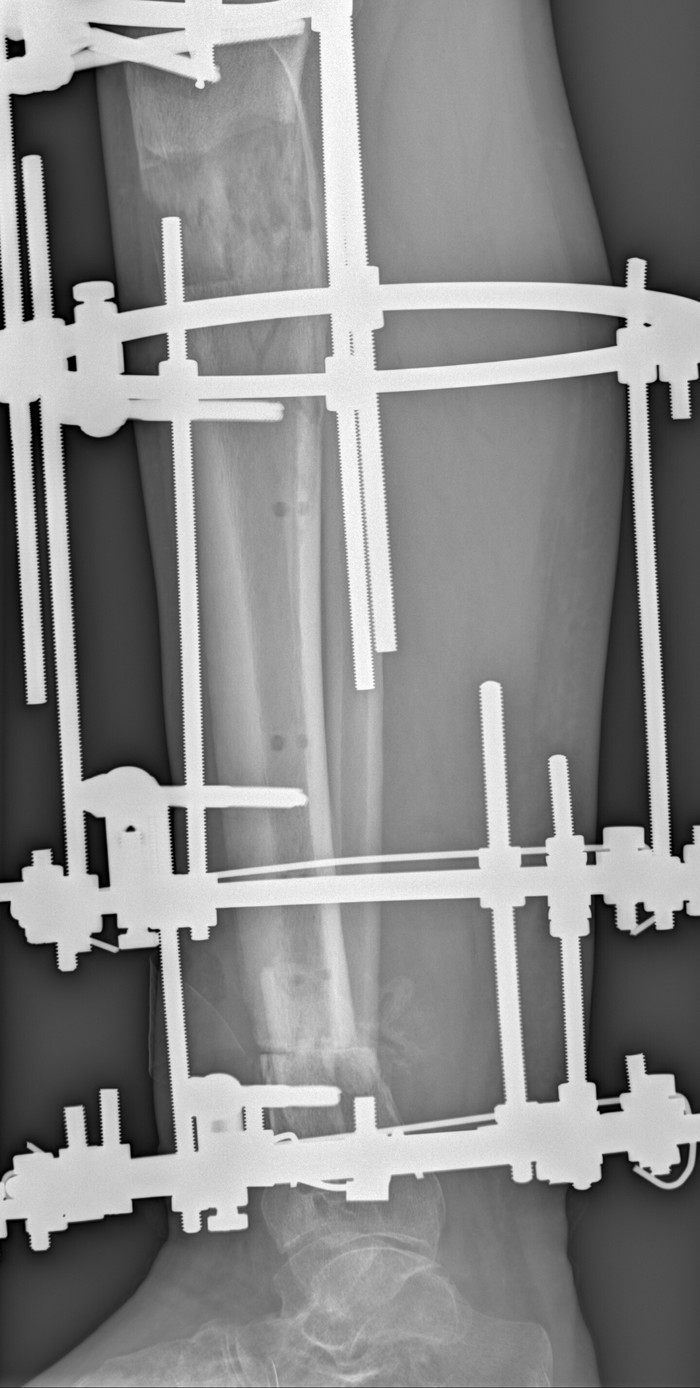

Травма голени. Мой путь. Часть 4

Здравствуйте. Настало время очеродного поста о моих злоключениях с поломаной ногой.

В качестве ремарки отвечу на часто задаваемый вопрос "для чего это?". Нет, это не для того чтоб меня пожалелибольше людей. И не для того чтоб показать невеликий уровень моего графоманства. Но если моя история подскажет кому-то попавшему в подобную беду, успокоит, подскажет что будет дальше, то я не зря печатал все эти буковки.

Итак в прошлом посте я остановился на том что закончил вытягивать кость в области искуственного перелома (дальше я буду по простому называть эту область "сверху") и стягивать кости на участке где удалили нежизнеспособную кость (дальше будет соответственно "снизу"). И вот я отправил весть об этом событии травматологу, который ставил аппарат. В ответ получил от него дату госпитализации на операцию по адаптации поверхностей, которые дотянулись друг до друга (снизу). Пришлось опять сдавать анализы в поликлинике. Обращу внимание, что анализы на инфекции (ВИЧ, Гепатит и пр) были годны и я просто получил дубликаты.

Дома стало гораздо лучше. Перевязываюсь каждый день. Язва уменьшилась. Нога потихоньку перестала болеть. Сначала таблетка обезболивания начинала мой день, в течение месяца стал пить пару раз в неделю, когда нужно куда-то далеко идти (в суд, например). Примерно через месяц я стал ходить с одним костылем и нагружать ногу. Сначала на обезболивающем, опираясь на стенку и предметы мебели. Потом и просто так. И вот, совсем недавно, я осмелел и стал ходить совсем без костылей. Пока по квартире. Вот такие достижения н сегодняшний день. На контрольных рентгенах вверху нарастает регенерат, внизу начинает формироваться костная мозоль, ещё незначительно, но вроде признаки есть

Через несколько дней мне назначили операцию. Подготовка мне была знакома, не есть, не пить и клизма. Утром знакомой дорогой в операционную, перекладываюсь на стол, укол в вену... И я просыпаюсь в палате, но на этот раз от сильного озноба, зуб на зуб не попадает. И тошнит, сильно. Ни о какой еде в этот день я даже не думал. На фоне обезболивания всё утихло. На ноге стоит тот самый аппарат Илизарова. Поощущениям тяжелый, но терпимо. Болит не сильно, скорее мешается. Мне объяснили что удалили 4,5 см нежизнеспособной кости. На следующий день я смог поворачиваться на бока Не удобно, колено на излом, и я выпросил подушечку. К вечеру я даже смог встать на костыли. На 3-й день я стал приступать на ногу (это разрешается на таком аппарате). Каждый день перевязки. И я стал ждать следующего этапа.

Следующая операция была еще через неделю (уже третья в этой больнице). Мне предполагалось сделать искуственный перелом в верхней части большеберцовой кости. А после, подкручивая гайки аппарата растянуть этот перелом на нужные мне сантиметры, дабы заместить дефект. Опять голод с вечера, клизма, укол, головокружение. И я просыпаюсь в своей палате. Озноба и тошноты в этот раз не было. Зато была боль под коленкой. И стало очень тяжело поднимать ногу, весь вес аппарата и голени был теперь на двух шпильках под коленом. К вечеру я смог поесть, утром уже встал на костыли. Нога болела и, что плохо, поднялась температура до 38. Мне делали обезболивающие, сменили антибиотики. Через неделю полегчало, температура спала.

Через неделю после операции нужно уже начинать вытяжение. Мне выдали ключи на 10 и рассказали какие гайки крутить. Крутить надо было по схеме 1/4 оборота через 6 часов. Я ставил будильник на телефоне. По началу было совсем не больно и даже забавно, сидишь, ключом в ноге ковыряешься. Через неделю мне сделали контрольный рентген, и убедившись что искуственный перелом начал расходиться меня выписали. Я поехал домой.

Первое время болей не было. Но через пару недель кожа на спицах натянулась и начала прорезываться. Вот тут и начался ад. Нога отекла, места входа спиц и шпилек воспалились, и было очень больно. К концу периода растяжения нога отекла настолько, что в колене не разгибалась. Я ел обезболивающие по нескольку раз в день, дошло до внутривенного введения. Это был самый сложный период лечения. Приходилось терпеть, потому что иного выхода не было. Забегая вперед я, даже обнаружив небольшую разницу в длине голеней, не хочу повторять эту пытку.